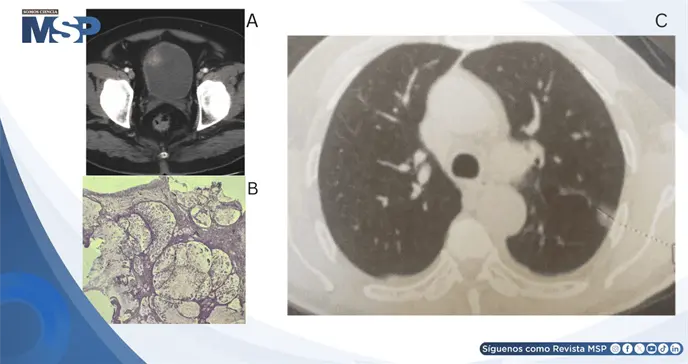

La tomografía computarizada mostró un tumor en la pared anterior de la vejiga con invasión de la grasa perivesical. La cistoscopia confirmó una lesión sólida de base amplia, con cuello vesical macroscópicamente normal.

Tras la resección transuretral profunda del tumor, el estudio anatomopatológico evidenció abundante mucina extracelular con células tumorales flotando en lagos de mucina, formación de nódulos mucosos en más del 80% del espécimen e invasión del músculo detrusor, hallazgos diagnósticos de adenocarcinoma mucinoso de células en anillo de sello.

Para descartar un origen secundario, se realizó colonoscopia total sin hallazgos patológicos, y el CEA sérico fue de 0,9 ng/mL, dentro del rango normal. La TC de extensión identificó un nódulo pulmonar de 14 mm sugestivo de metástasis y múltiples lesiones óseas líticas, confirmando la diseminación a distancia.